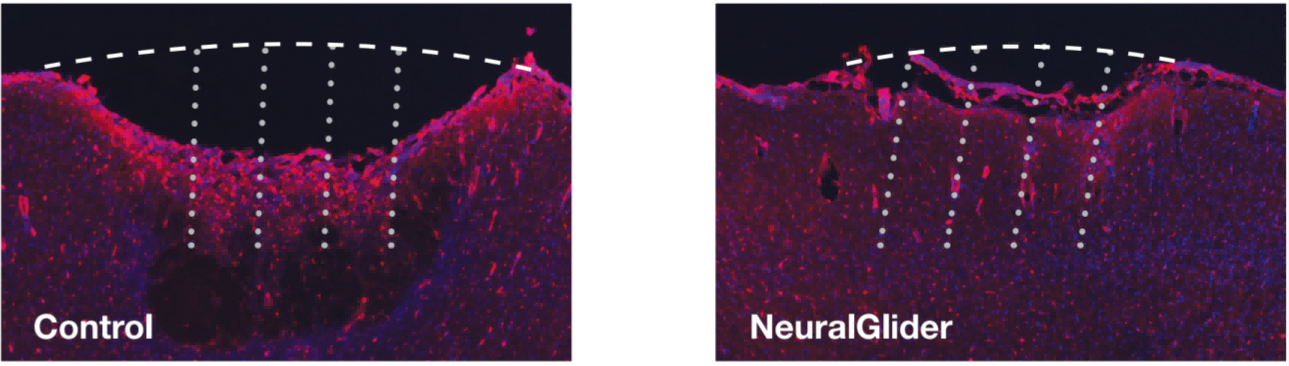

与左图的标准对照插入相比,右图的 NeuralGlider Inserter 减少了体 内皮质表面损伤,以及微丝阵列插入部位血脑 屏障的渗漏(IgG 染色, 红色)。图像展示的是植入 2x4、50 µm 微丝阵列 2 周后,20µm 大 鼠皮质切片。 |